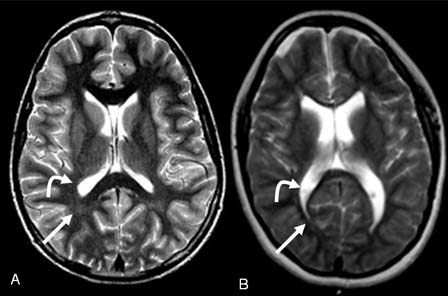

Leucomalácia periventricular. A Figura A é de uma menina normal de 14 anos de idade: a seta curva mostra o ventrículo lateral normal e a seta reta mostra a substância branca normal. A Figura B é de uma menina de 14 anos de idade com paralisia cerebral (PC): a seta curva mostra o ventrículo lateral aumentado e a seta reta mostra o volume diminuído da substância branca em decorrência da leucomalácia periventricular

Cortesia de Noriko Solomon, Professora Assistente de Radiologia, David Geffen School of Medicine at UCLA, Los Angeles